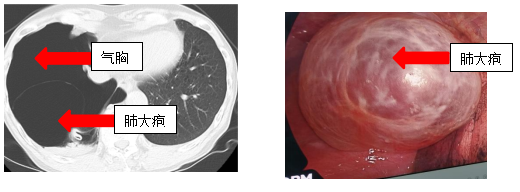

近日,北京市垂杨柳医院胸外科接诊了一位自发性气胸的患者。三天前,患者在经历剧烈咳嗽后,出现了轻度胸闷、呼吸困难和气短的症状。由于症状相对较轻,加之患者过去有过类似情况并自行缓解的经历,因此并未给予足够重视。然而,随着时间的推移,患者气短症状逐渐加剧,严重影响了日常生活。于是患者来到医院胸外科进行检查。胸部CT扫描显示右侧气胸,肺压缩约60%。鉴于患者肺部压缩程度大,症状严重,胸外科医疗团队立即为患者进行了急诊胸腔闭式引流术,患者的气短症状随即得到缓解。然而,治疗并未就此结束,胸部CT还显示了右侧存在多个肺大疱,其中最大的直径达8.6厘米。结合患者症状反复发作已符合胸腔镜肺手术治疗的指征,同时,患者巨大肺大疱导致正常肺功能受限,也具有手术治疗指征。因此,在全面评估后,患者在微创胸腔镜手术治疗后顺利出院。

肺大疱(肺大泡)是由于肺泡腔内压力异常升高,导致肺泡壁破裂并相互融合形成的含气囊腔。它常见于慢性阻塞性肺疾病(COPD)、肺气肿患者,也可能因感染、创伤或先天因素引发。肺大疱本身可能无症状,但若破裂可能导致气胸,引发呼吸困难甚至危及生命。

1.精准诊断:通过胸部CT、肺功能检查等明确肺大疱位置、大小及肺功能损伤程度。